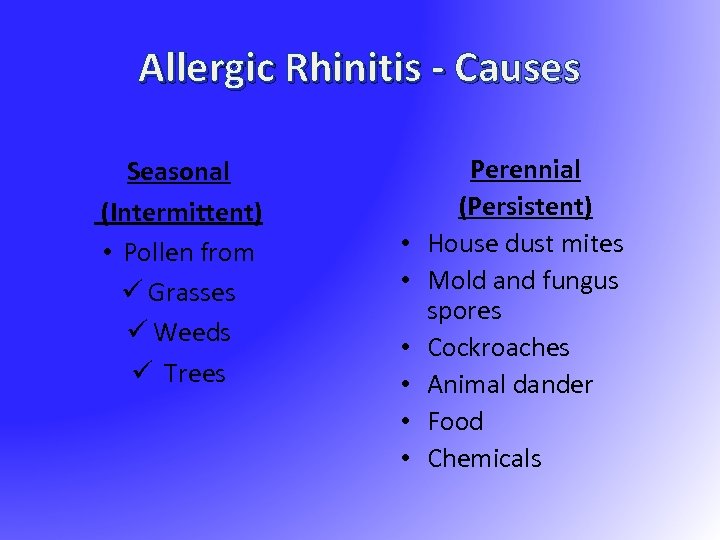

Allergic Rhinitis - Causes Seasonal (Intermittent) • Pollen from ü Grasses ü Weeds ü Trees • • • Perennial (Persistent) House dust mites Mold and fungus spores Cockroaches Animal dander Food Chemicals

Allergic Rhinitis - Causes Seasonal (Intermittent) • Pollen from ü Grasses ü Weeds ü Trees • • • Perennial (Persistent) House dust mites Mold and fungus spores Cockroaches Animal dander Food Chemicals